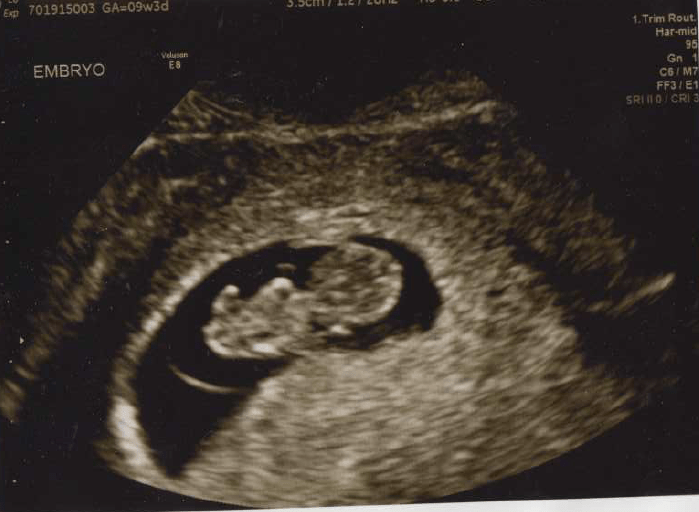

April 9th – Sarah heard the heartbeat for the first time and Eitan got to tune in via FaceTime. Being pregnant during COVID-19 is unique as they don’t let the fathers attend the ultrasound to minimize the risk of contagion. Hearing that heartbeat was pretty amazing!

April 27th – I had an unplanned ultrasound due to some weird symptoms, so hearing the heartbeat this time was even more exciting. Also, the ultrasound technician made a guess at the gender but Sarah and Eitan kept their lips sealed, no easy task for Sarah who wanted to announce to the world she was pregnant the moment she found out. You know the quote “Patience is a virtue”? Sarah has none of that… Like zero of that.